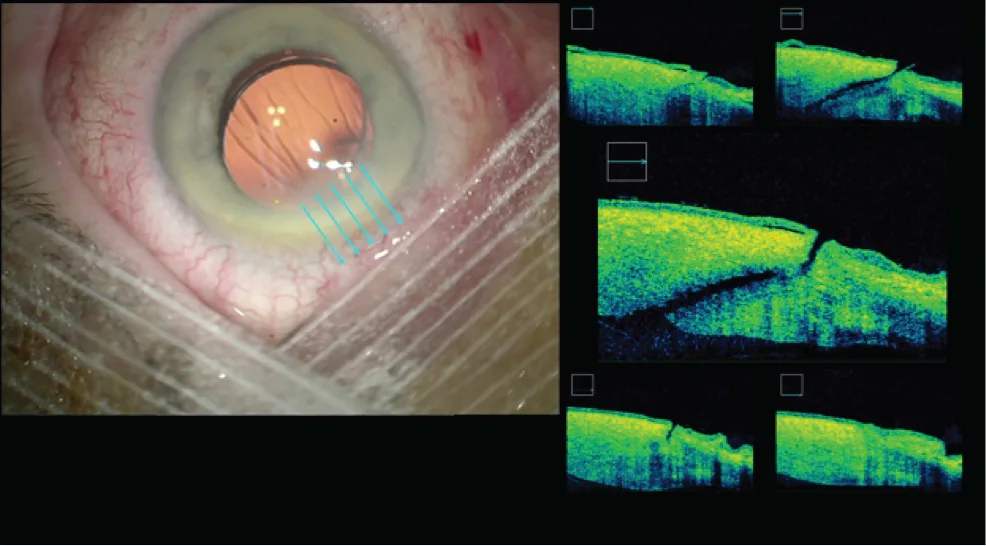

Figure 3.7. OCT peropératoire de l’incision principale (2,2 mm), juste après réalisation de celle-ci (A)

Figure 3.7. OCT peropératoire de l’incision principale (2,2 mm), et en fi n d’intervention après l’implantation (B).

Contrôler l’astigmatisme cornéen grâce à l’incision

Les incisions transfixiantes de cornée peuvent aussi devenir un moyen de contrôler l’astigmatisme cornéen [4]. Un certain nombre de chirurgiens placent l’axe de l’incision principale sur le méridien le plus cambré, voire élargissent l’incision en fin de procédure (figure 3.10 et vidéo 9, cas 10 ), afin de compenser naturellement l’astigmatisme cornéen. Cette méthode simple, qui nécessite cependant une grande flexibilité de la technique opératoire voire un changement de main, permet de contrôler les faibles astigmatismes cornéens, ce qui peut être précieux en cas d’implantation multifocale dans les cas limites où une optique multifocale–torique n’est pas indiquée. Cette méthode est cependant sujette à une grande variabilité de l’effet final. Plus récemment, nous avons montré que les propriétés biomécaniques de la cornée analysées par ORA ® constituaient un cofacteur majeur de l’astigmatisme induit [5]. En résumé, une cornée « souple » contribue à augmenter l’astigmatisme induit, alors qu’une cornée rigide est plus influencée par la largeur ou la construction de l’incision.

Figure 3.10. En fin de phacoémulsification, élargissement d’une incision de 1,8 à 2,2 mm avant insertion d’un implant hydrophobe.